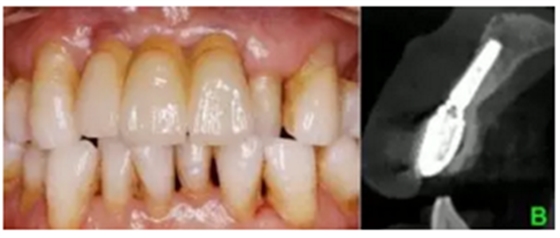

結(jié)合PRF的位點(diǎn)保存術(shù)后牙槽嵴輪廓豐滿,CBCT示骨量充足,數(shù)字化種植外科導(dǎo)板輔助下植體植入三維位置精確,種植體骨結(jié)合良好,數(shù)字化口掃系統(tǒng)數(shù)據(jù)采集高效、精確,臨時(shí)修復(fù)體戴入,軟組織成形,最終修復(fù)體戴入后穩(wěn)定、密合,牙齦軟組織色澤形態(tài)正常,美學(xué)效果良好。

(3)數(shù)字化3D種植外科導(dǎo)板引導(dǎo)下Straumann 3.3x12 NC 種植體行延期種植